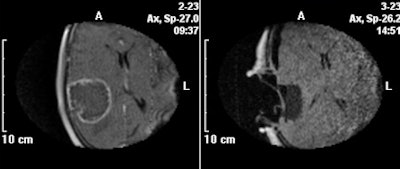

The use of MRI -- provided by a mobile intraoperative ultralow-field system (PoleStar, Odin Medical Technologies) -- during surgery led to extended tumor resection in one-third of the patients, according to lead author Dr. Christian Senft of the Klinik für Neurochirurgie and colleagues. All but one patient (96%) had a complete tumor resection compared with only 17 patients (68%) who had conventional microsurgery.

All patients had an MRI examination both within a week and three days after surgery. Their images were reviewed by an experienced neuroradiologist to establish the extent of resection and to undertake volumetric analyses of the tumors and tumor residues. This radiologist was blinded to the patient group status.

Sixteen (67%) of the patients in the intraoperative MRI group were stable six months following surgery, compared with nine (36%) in the control group, the researchers reported. The disease progressed in eight (33%) patients in the MRI group, compared with 16 (64%) in the control group, one of whom had died.